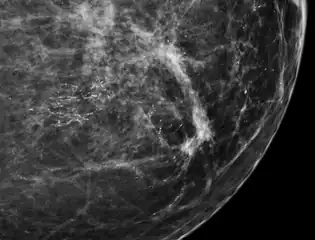

Microcalcifications are tiny deposits of calcium salts that are too small to be felt but can be detected by imaging.[1]

They can be scattered throughout the mammary gland, or occur in clusters. Microcalcifications can be an early sign of breast cancer. Based on morphology, it is possible to classify by radiography how likely microcalcifications are to indicate cancer. [2]

In breast

Microcalcifications in the breast are made up of calcium phosphate or calcium oxalate. When consisting of calcium phosphate, they are usually dystrophic calcifications (occurring in degenerated or necrotic tissue).[3] Yet, the mechanism of their formation is not fully known.[4]